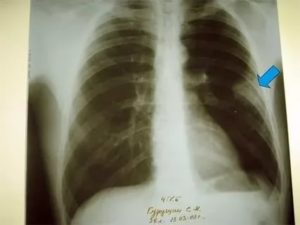

Достоверная визуальная диагностика плевральных шварт возможна только если соединительно-тканные образования больше 1 см в толщину. В противном случае тень от спаек накладывается на ткань легкого и не видна на рентгенограмме. При указании на характерные жалобы, которые возникли и сохраняются после перенесенного плеврита, требуется проведение дополнительных исследований таких, как:

Для обнаружения легочных заболеваний в первую очередь используется флюорография. Эту процедуру необходимо проводить ежегодно, в основном она направлена на выявление ранней стадии туберкулеза. Однако опытный рентгенолог может выявить на снимке образовавшиеся плевральные спайки, которые выглядят тенями. Причем форма их не меняется в зависимости от вдоха и выдоха.

При необходимости дополнительно назначается рентген. Как правило, спайки располагаются в нижней части легкого. При этом будет более темная картинка, а также может быть частичная деформация грудной клетки и диафрагмы.

На снимках тяжи выглядят затемненными участками легочного поля с усиленным сосудисто-соединительнотканным рисунком. При множественных поражениях определяются диффузные затемнения. Также возможно снижение высоты стояния ребер, уменьшение межреберного пространства и смещение органов.